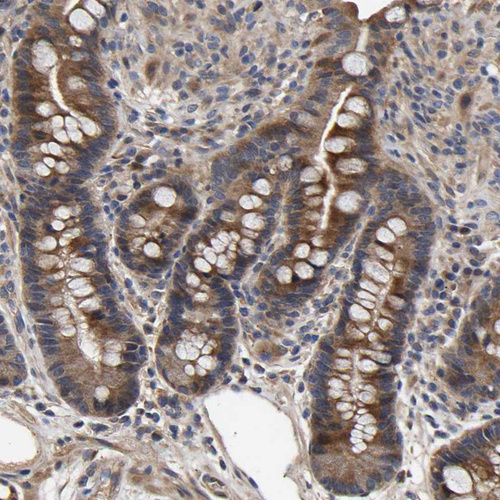

Immunohistochemical staining of human cerebral cortex, gastrointestinal, lymphoid tissues and testis using Anti-CCDC155 antibody HPA019940 (A) shows similar protein distribution across tissues to independent antibody HPA019937 (B).